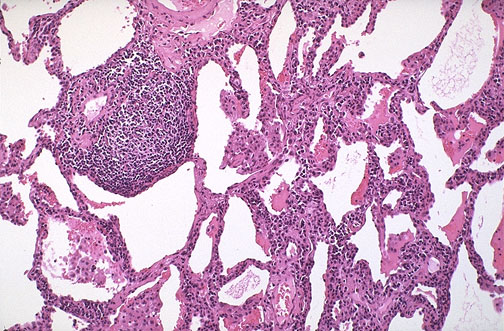

Lymphoid interstitial pneumonitis (LIP) is seen here in lung at medium power. LIP is not seen in adults with AIDS.